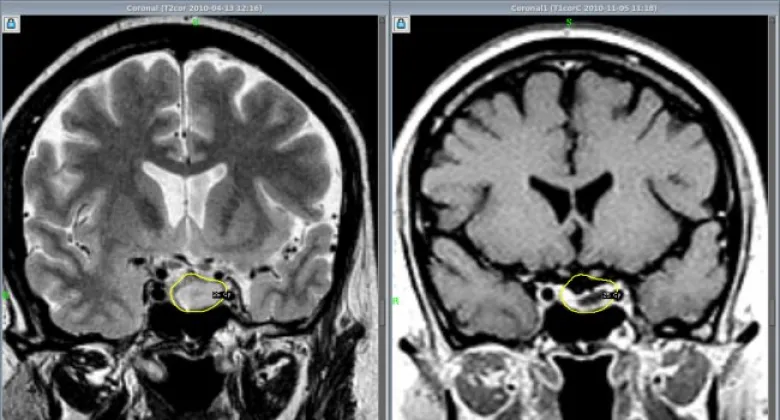

До недавних пор такие новообразования в МЦ «Астхик» удаляли с применением хирургического микроскопа. Теперь в медцентре внедряют и другой метод удаления аденом гипофиза – с помощью эндоскопа. Этот метод до недавних пор в Армении не применялся, и обучать ему специалистов в рамках одного из проектов благотворительного фонда «Вива» будет известный нейрохирург Вилен Азизян (Россия). В медицинском центре «Астхик» он уже провел три операции по удалению аденом гипофиза. Ассистировали ему армянские специалисты, которые в дальнейшем научатся проводить такие операции самостоятельно.

Аветис Киракосян, руководитель отделения нейрохирургии МЦ «Астхик», рассказал журналистам о том, что для внедрения эндоскопического метода удаления опухолей гипофиза был выбран медцентр «Астхик», так как материально-техническая база центра соответствует всем требованиям к проведению этих операций. Специалист уверен, что если в центре будут применяться оба метода, это поможет достигать более значительных результатов.

«В зарубежных медицинских центрах, где я проходил переподготовку, совмещают микроскопический и эндоскопический методы. После работы микроскопом проводят ревизию операционной области с помощью эндоскопа – без лишних разрезов через нос пациента вводят эндоскоп с камерой, осматривают область, иногда можно бывает обнаружить небольшие куски, которые остались вне поля зрения микроскопа, а эндоскоп может обеспечить более широкое поле зрения», - объяснил специалист.

По его словам, эндоскопическое удаление аденом гипофиза считается менее травматичным и менее инвазивным, чем микроскопическое удаление. Так или иначе, некоторым пациентам может потребоваться один из методов, некоторым – сразу оба, поэтому будет большим плюсом, если хирург будет одинаково хорошо владеть обоими методами.